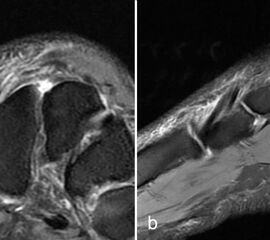

Zwischen der plantaren Platte und der Grundphalanx ist in der Mittellinie des Gelenkes ein kleiner Rezessus vorhanden (Abb. 9).

Dieser flüssigkeitsgefüllte Raum darf nicht als Ruptur der plantaren Platte fehlinterpretiert werden 23. Verletzungen der plantaren Platte erfassen immer auch den medialen oder lateralen Zügel.

Die sagittalen PD FS Schichten im medialen und lateralen Bereich der plantaren Platte (a, c) zeigen eine völlig unauffällige,  Der kleine Flüssigkeitseinschluss in der Mittellinie der Zehe (b, Pfeil) entspricht einem physiolo